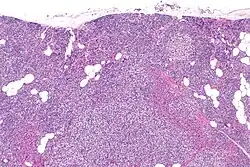

Hyperparathyroidism, in general, is caused by either tumorous growth in one or more parathyroid glands or a prolonged decrease in blood calcium levels or hypocalcaemia which in turn stimulates the production of parathyroid hormone release from the parathyroid gland.[10][11] The parathyroid gland is located beside the thyroid gland in the neck, below and in front of the larynx and above the trachea. It is composed of four glands in total that monitor blood calcium levels via the calcium sensing receptors, a g-coupled protein receptor.[12] The parathyroid glands main role is calcium homeostasis.[13][12] Histologically, these glands are composed of chief cells and oxyphil cells with the chief cell primarily responsible for the storing and release of parathyroid hormone. These cells are arranged in a pseudo-follicular pattern similar to the thyroid follicles. Keratin staining is used to image the parathyroid hormone granules.[9][14]

Primary hyperplasia of the parathyroid gland, results from both hypocalcaemia and increased phosphate levels by decreasing expression of calcium sensing receptors and vitamin D receptors at the parathyroid gland.[8][4] These decreases in receptor expression lead to hyperfunctioning of the parathyroid. Hyperfunction of the parathyroid gland is thought to exacerbate primary hyperplasia which evolves further to a secondary more aggressive hyperplasia. Histologically, these hyperplasic glands can be either diffuse or nodular.[24] Primary hyperplasia, usually resulting in diffuse polyclonal growth is manly related to reversible secondary hyperparathyroidism. Secondary hyperplasia of the parathyroid gland is more often a nodular, monoclonal growth that sustains secondary hyperparathyroidism and is the catalyst in the progression to tertiary hyperparathyroidism. Nodular hyperplastic glands in tertiary hyperparathyroidism are distinctly larger in both absolute size and weight up to 20-40-fold increases have been reported.[25][26][24]

Parathyroid glands are normally composed of chief cells, adipocytes and scattered oxyphil cells.[27][14] Chief cells are thought to be responsible for the production, storage and secretion of parathyroid hormone. These cells appear light and dark with a prominent Golgi body and endoplasmic reticulum. In electron micrographs, secretory vesicles can be seen in and around the Golgi and at the cell membrane. These cells also contain prominent cytoplasmic adipose.[27][14] Upon onset of hyperplasia these cells are described as having a nodular pattern with enlargement of protein synthesis machinery such as the endoplasmic reticulum and Golgi. Increased secretory vesicles are seen and decreased intercellular fat is characteristic.[27][24] Oxyphil cells also appear hyperplasic however, these cells are much less prominent.